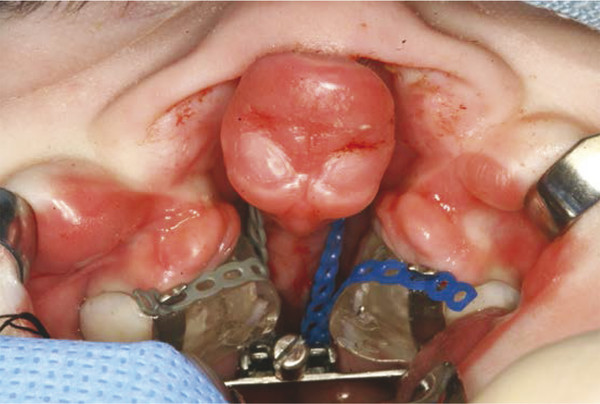

Infants with bilateral clefts are treated at a slightly older age than those with unilateral clefts (4–8 weeks of age). In the bilateral complete cleft, the anterior margins of the palatal shelves are frequently narrow and the premaxilla on the vomer stalk is markedly anterior and, in some cases, twisted in a lateral or superior/inferior direction. The goal of this treatment is to move the anterior aspect of the palatal shelves apart (transversely), while at the same time retracting the premaxilla to a position between the palatal shelves (Fig. 12‑8).

In the operating room, the junction of the premaxilla and vomer is visualized, and two points are marked along a horizontal line bisecting the cephalad–caudal width of the vomer, approximately 1 and 3 mm posterior to that junction (Fig. 12‑9). Using a handheld chuck and a twist drill (Peeso endodontic), two parallel channels are drilled through the vomer at these marks. A U-shaped 0.020 stainless steel wire (8–10 mm in length) is then prepared for insertion through these channels. Elastic chain is then attached to the more distal arm of the “U,” and it is passed through the vomer. Elastic chain is applied to the distal aspect, and the wire bent to prevent its loss (Fig. 12‑10 and Fig. 12‑11).

The elastic chains are then pulled through the appliance, as it is seated on the palate.

The appliance is secured with four pins in the same manner as the dental maintenance alternative (DMA). The elastic chains are then moved anteriorly and are separately attached with moderate force to the cleats at the anterior edge of each palatal shelf. The activation screw, which is in the posterior midline, is activated (Fig. 12‑12).

The expansion screw in the bilateral appliance (elastomeric chain premaxillary retraction [ECPR]) moves the palatal shelves in a “V” direction and provides enough width to accept the premaxilla. At the same time, the premaxilla is retracted by the elastic chain. The amount of expansion must be closely monitored to prevent a flattening of the nasal tip, excessive width at the alar base, and a prominence of the nasal eminences of the maxillary bone. The patient is monitored at 1 week, 3 weeks, and 5 weeks to ensure that the screw is activated appropriately and to allow the elastic chains to be reactivated. Feeding is again the main postoperative concern. In addition, mucus and milk curd accumulate between the palatal shelves and are cleaned with suction at each visit.